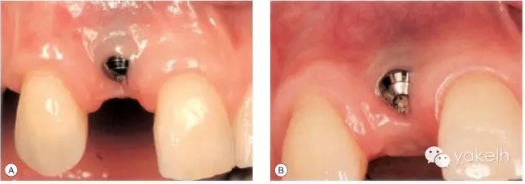

患者先天缺失側(cè)切牙,同時(shí)由于外傷UR1缺失。UR1種植修復(fù)。該種植冠大約有2mm 的牙齦退縮,與UL1相比,該修復(fù)冠較長(zhǎng)(圖.8A)。這是由于種植體植入位置過深而導(dǎo)致的(圖.8B)。

圖.8 種植體植入過深,引起牙齦退縮以及修復(fù)冠過長(zhǎng)。